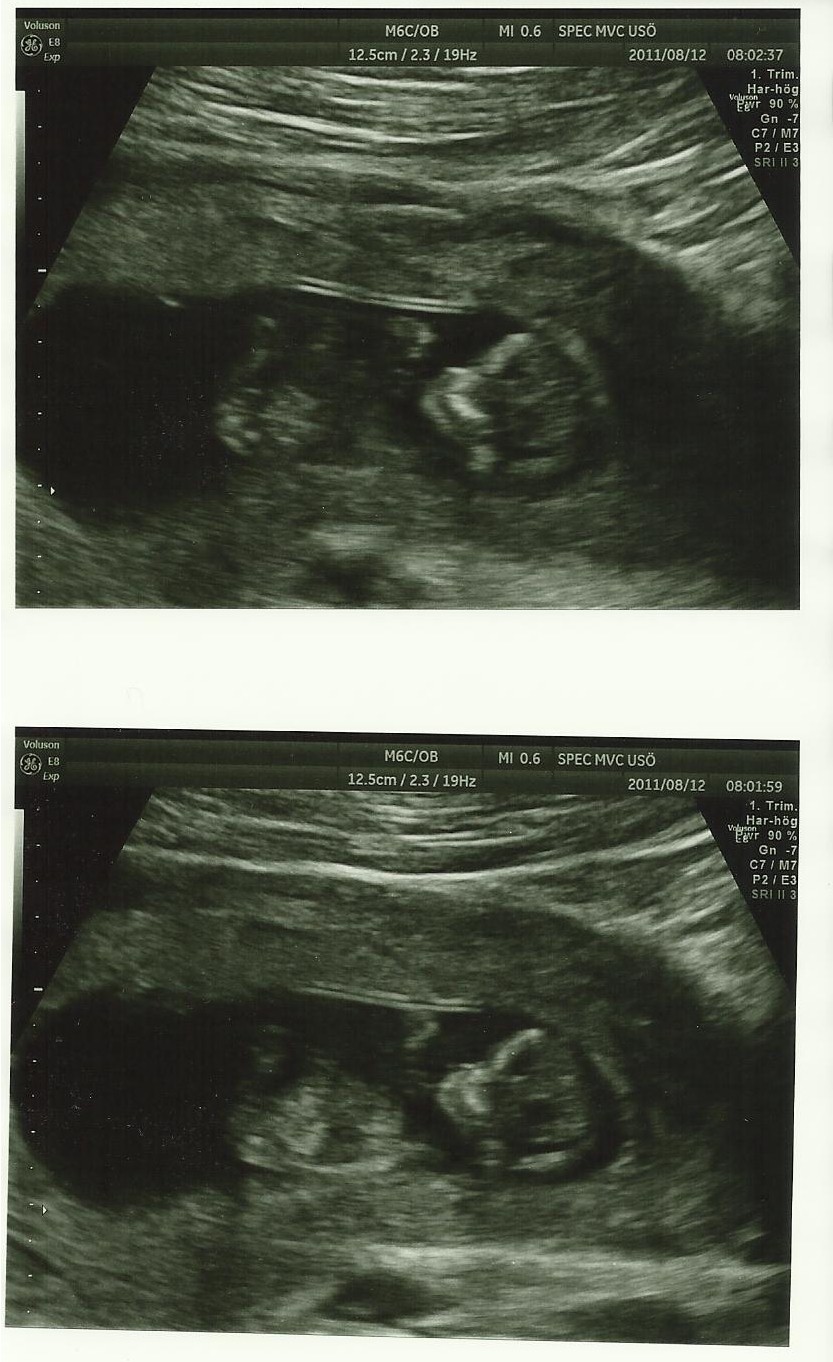

I fredags var vi på ultraljud och fick se den lilla korven sprattla runt och veva med händerna. Fantastiskt.